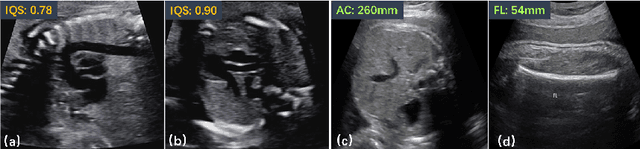

Abstract:Fetal pose estimation in 3D ultrasound (US) involves identifying a set of associated fetal anatomical landmarks. Its primary objective is to provide comprehensive information about the fetus through landmark connections, thus benefiting various critical applications, such as biometric measurements, plane localization, and fetal movement monitoring. However, accurately estimating the 3D fetal pose in US volume has several challenges, including poor image quality, limited GPU memory for tackling high dimensional data, symmetrical or ambiguous anatomical structures, and considerable variations in fetal poses. In this study, we propose a novel 3D fetal pose estimation framework (called FetusMapV2) to overcome the above challenges. Our contribution is three-fold. First, we propose a heuristic scheme that explores the complementary network structure-unconstrained and activation-unreserved GPU memory management approaches, which can enlarge the input image resolution for better results under limited GPU memory. Second, we design a novel Pair Loss to mitigate confusion caused by symmetrical and similar anatomical structures. It separates the hidden classification task from the landmark localization task and thus progressively eases model learning. Last, we propose a shape priors-based self-supervised learning by selecting the relatively stable landmarks to refine the pose online. Extensive experiments and diverse applications on a large-scale fetal US dataset including 1000 volumes with 22 landmarks per volume demonstrate that our method outperforms other strong competitors.

Abstract:Regression learning is classic and fundamental for medical image analysis. It provides the continuous mapping for many critical applications, like the attribute estimation, object detection, segmentation and non-rigid registration. However, previous studies mainly took the case-wise criteria, like the mean square errors, as the optimization objectives. They ignored the very important population-wise correlation criterion, which is exactly the final evaluation metric in many tasks. In this work, we propose to revisit the classic regression tasks with novel investigations on directly optimizing the fine-grained correlation losses. We mainly explore two complementary correlation indexes as learnable losses: Pearson linear correlation (PLC) and Spearman rank correlation (SRC). The contributions of this paper are two folds. First, for the PLC on global level, we propose a strategy to make it robust against the outliers and regularize the key distribution factors. These efforts significantly stabilize the learning and magnify the efficacy of PLC. Second, for the SRC on local level, we propose a coarse-to-fine scheme to ease the learning of the exact ranking order among samples. Specifically, we convert the learning for the ranking of samples into the learning of similarity relationships among samples. We extensively validate our method on two typical ultrasound image regression tasks, including the image quality assessment and bio-metric measurement. Experiments prove that, with the fine-grained guidance in directly optimizing the correlation, the regression performances are significantly improved. Our proposed correlation losses are general and can be extended to more important applications.